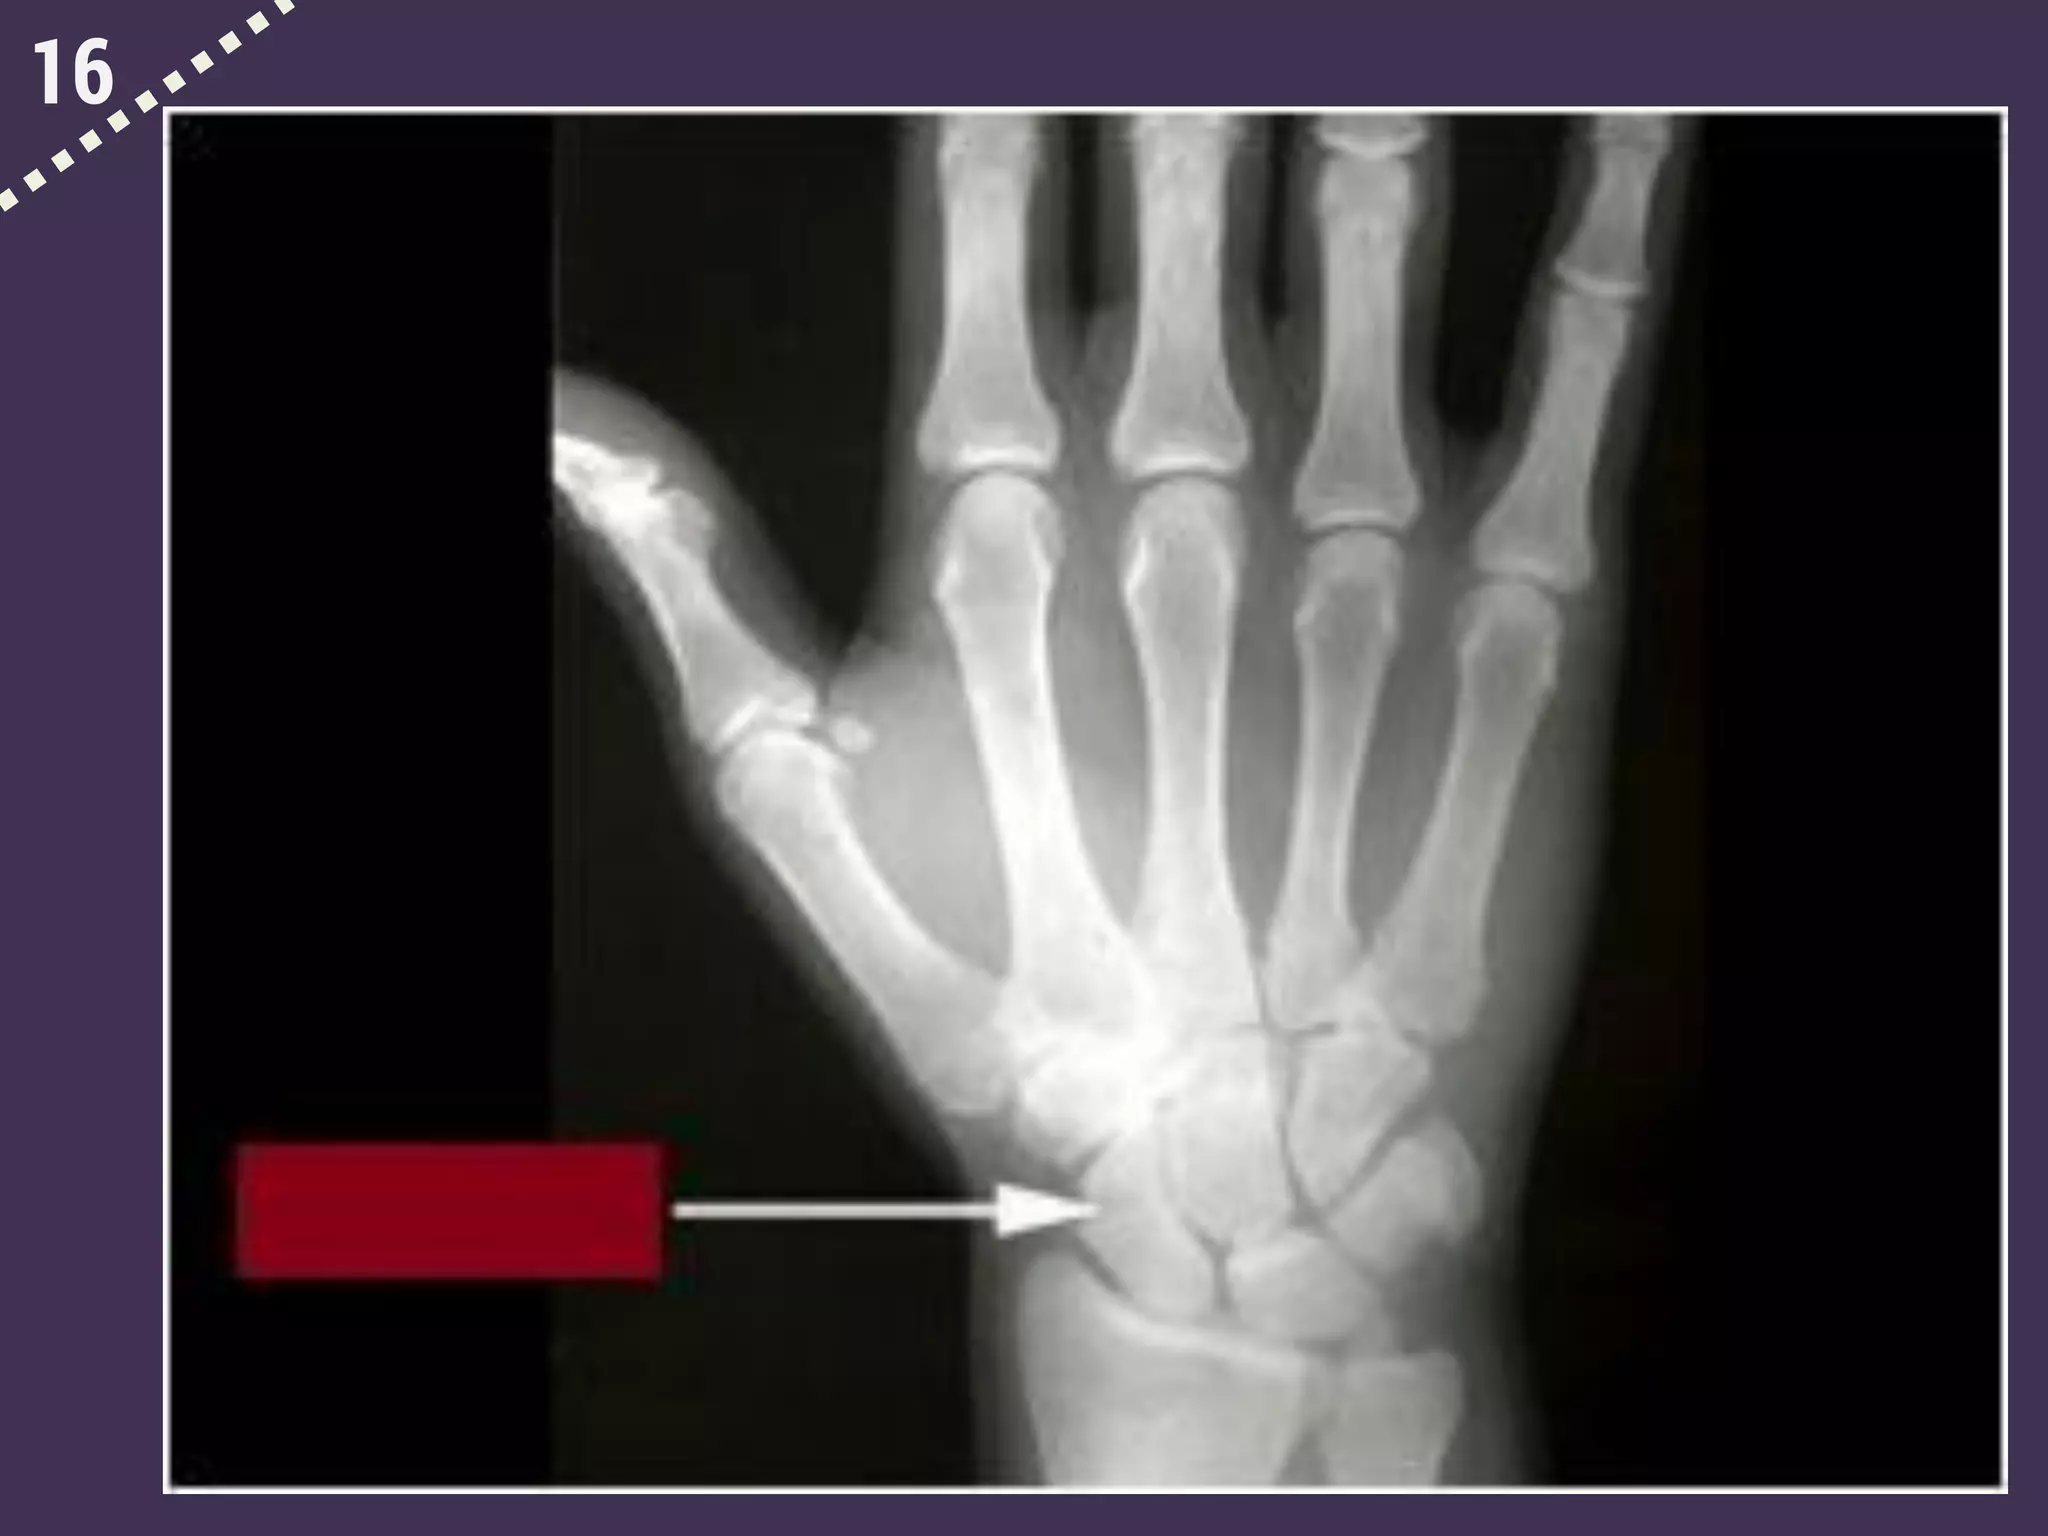

16

Connect the two visuals.

Both come from “scaph” meaning “ship”

(bathyscaphe, scaphoid bone).